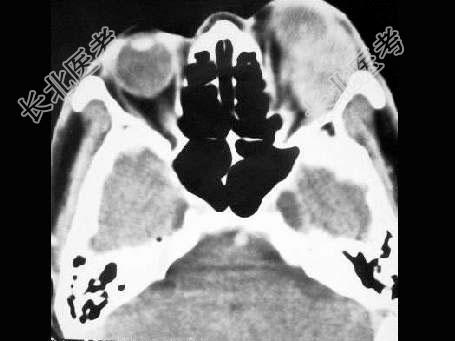

- 单项选择题男,45岁, 左眼疼痛伴视力下降一个多月,左眼明显外突, CT扫描如图所示,最可能的诊断是 ( )

A、左侧眶内炎性假瘤

B、左眶内血管瘤

C、左眶内纤维瘤

D、左眶内结核

E、左眶内转移瘤